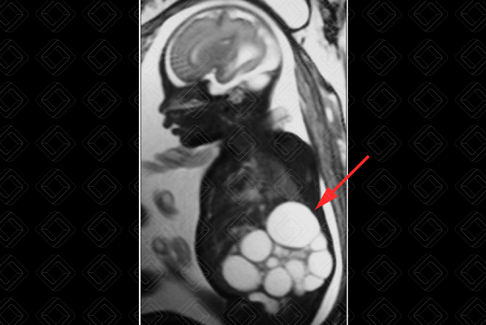

Texto alternativo para a imagem Figura 1. Créditos: Dra. Elazir Mota - Rio de Janeiro/RJ

Texto alternativo para a imagem Figura 2. Créditos: Dra. Elazir Mota - Rio de Janeiro/RJ

Descrição das figuras 1 e 2: Ressonância magnética fetal - sequência ponderada em T2 apresentando múltiplas formações ovaladas com hipersinal em T2 (setas vermelhas), compatível com cistos, não comunicantes e de tamanhos variados na loja renal esquerda. Observe ausência de parênquima renal adjacente. Achados muito sugestivos de rim multicístico displásico esquerdo.

• Ressonância magnética do abdome: E sse exame é muito útil para avaliação intra-útero quando a ultrassonografia fetal não consegue definir com exatidão o aspecto de imagem. Na ressonância magnética fetal, observam-se múltiplas imagens císticas, com hipersinal em T2, com tamanhos variados e não comunicantes (setas vermelhas) (figuras 1 e 2).